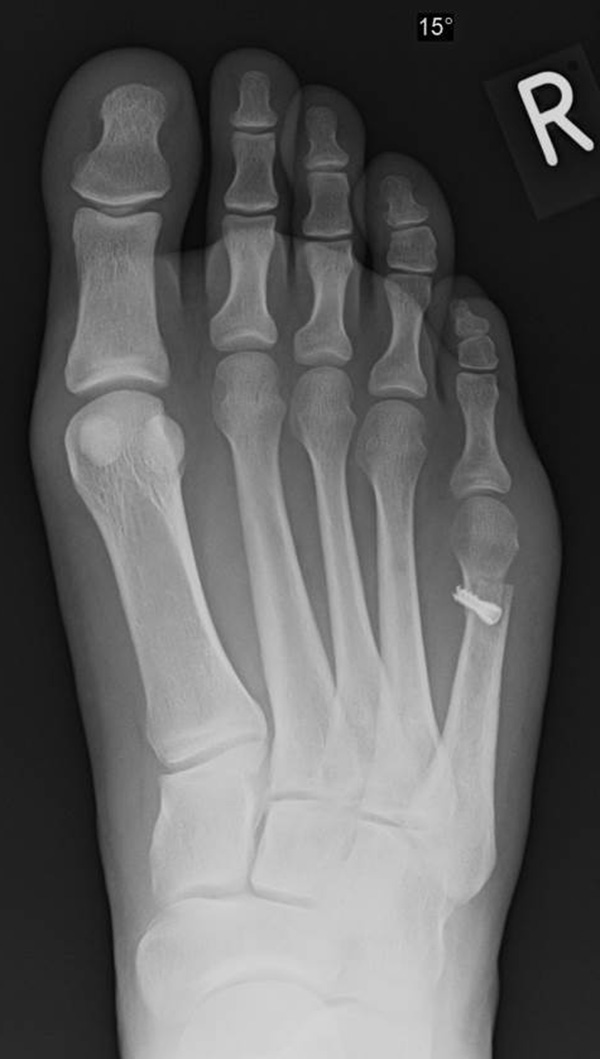

Abb. 7 a, b: Typ II Deformität mit prä- (a) und postoperativem Röntgenbild (b) mit K-Draht Osteosynthese und gleichzeitiger Hallux valgus Korrektur.

Abb. 8 a, b, c: Typ III Deformität mit prä- (a) und postoperativem Röntgenbild (b, c) mit Schrauben-Osteosynthese.